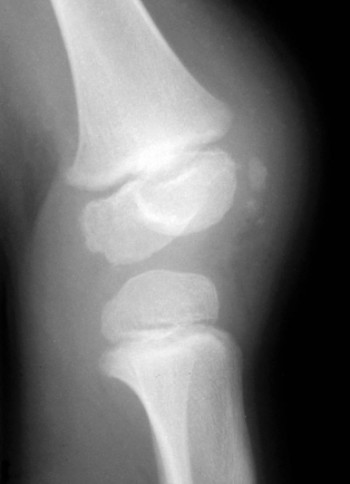

o قد يعانى المريض من آلام أو آلام مصحوبة بتورم ونقصان فى قوس الحركة (التهاب) فى مفاصل الركبة، الكاحل وبصورة أقل الرسغ والمرفق (الكوع) أو أصابع اليدين

o تظهر آلام المفاصل فى حوالى 56% أو أكثر من المرضى

o فى معظم الحالات تكون آلام المفاصل مصحوبة أيضاً بآلام وتورم فى الأنسجة الرخوة المحيطة بالمفاصل المصابة

o غالباً ما تكون آلام المفاصل مؤقتة لتختفى خلال أيام من ظهورها.